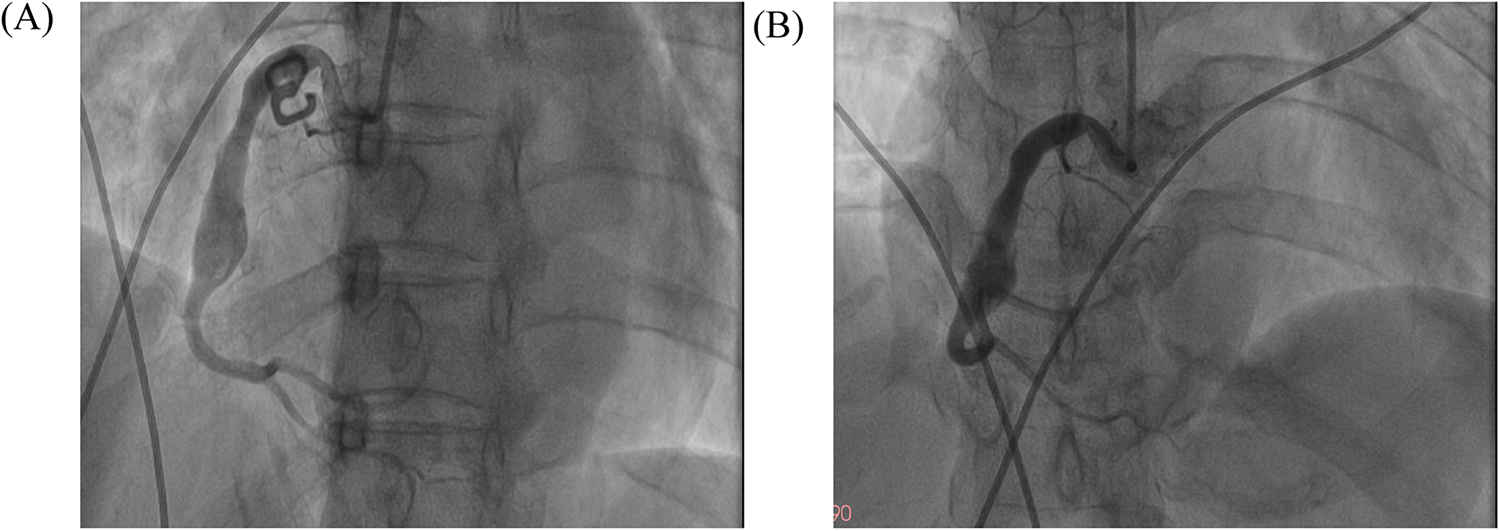

Repeat coronary angiography performed one week of intensive antithrombotic therapy demonstrated near-complete dissolution of the intracoronary thrombus within the aneurysmal segment, accompanied by restored laminar flow in the affected right coronary artery (Figure 3). However, the patient declined to undergo intravascular ultrasound for precise assessment of the intracoronary aneurysm due to financial constraints. In light of the potential for recurrent thrombosis, we determined that stenting should be recommended following the patient's discharge from the hospital, with adequate anticoagulation treatment. Throughout the hospitalization, the patient remained free from anginal symptoms or ischemic electrocardiographic changes. Upon discharge, a tailored regimen combining therapeutic-dose rivaroxaban (10 mg daily) with DAPT (aspirin 100 mg daily and clopidogrel 75 mg daily) was initiated. Surveillance at 1- and 3-month post-discharge follow-ups revealed no adverse cardiovascular events, including recurrent thrombosis, myocardial infarction, or bleeding complications, with echocardiography confirming preserved left ventricular ejection fraction (LVEF 64%). Based on this favorable clinical course, the antithrombotic regimen was transitioned to rivaroxaban 10 mg daily plus clopidogrel 75 mg daily following the three-month evaluation.

Figure 3

The images of follow-up coronary angiography. The images of follow-up coronary angiograms after the patient received intensive pharmacotherapy. (A) LAO 45°; (B) AP + CRA 20°.